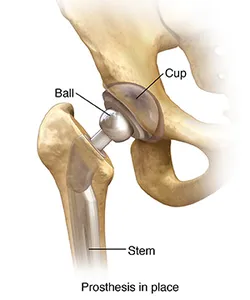

A prosthesis

An artificial ball replaces the head of the thighbone, and an artificial cup replaces the worn socket. A stem is inserted into the thigh bone to keep the ball in place. These parts connect to create your new artificial hip. A plastic liner is placed between the metal ball and cup to create a smooth surface for comfortable movement once you have healed.